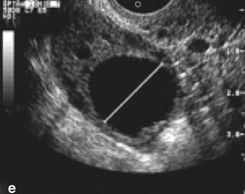

The dominant follicle typically reaches a size of 18 to 30 mm before ovulation. The dominant follicle appears simple (black in current standard formatting).

After ovulation, the dominant follicles no longer appears entirely black (simple). Instead, it shows internal echoes of hemorrhage and a mildly irregular and thickened wall. Prominent peripheral vascularity is also usually seen with Doppler studies.